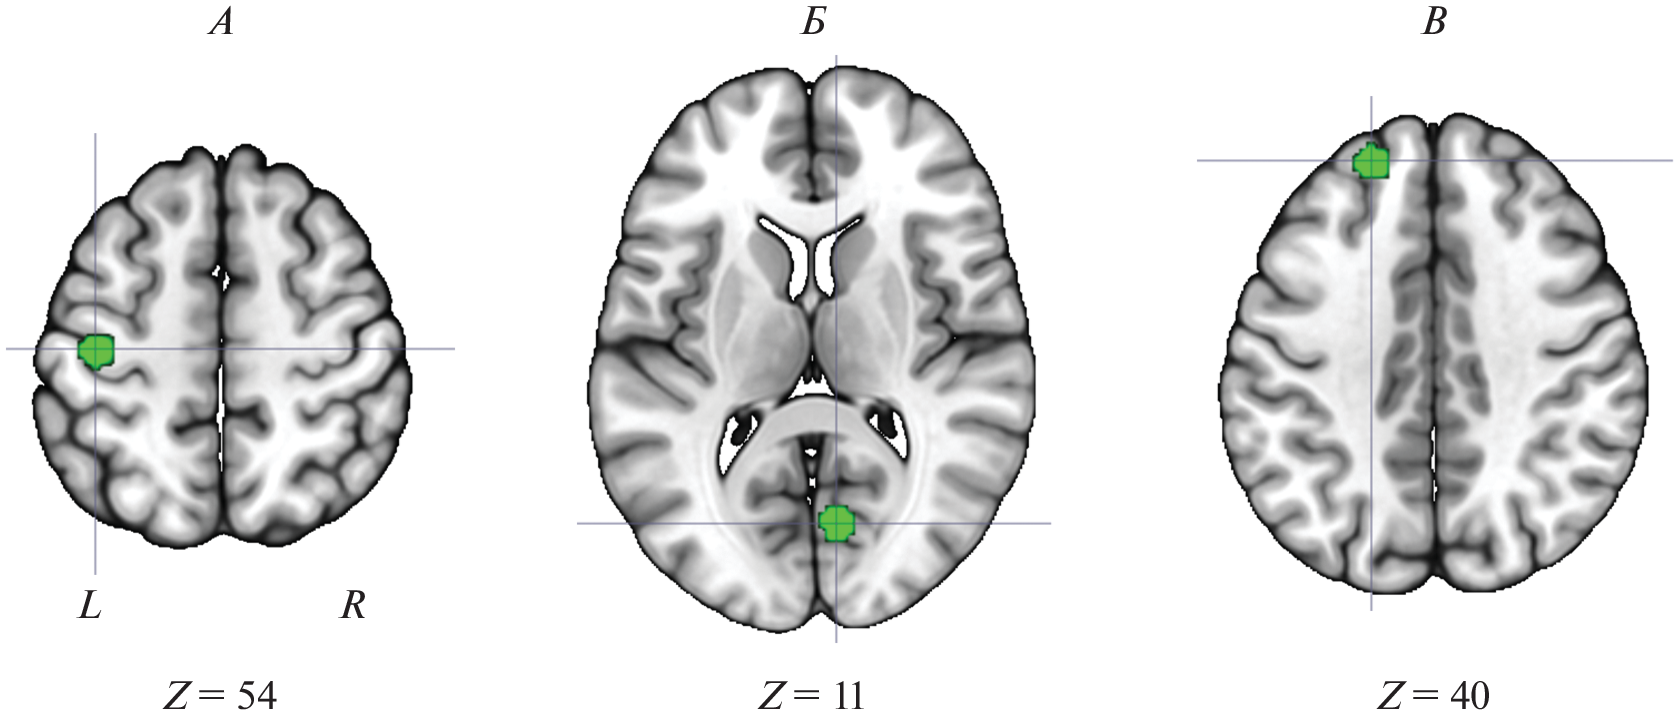

В настоящее время общепринятым является представление о том, что в основе работы мозга лежит системный принцип его функционирования. Вместе с тем, закономерности системной работы мозга изучены недостаточно полно. В данной работе исследование этих закономерностей проводилось в рамках развития представления о так называемых “скрытых” звеньях мозговых систем. Ранее по данным функциональной магнитно-резонансной томографии (фМРТ) авторами было показано, что целый ряд структур мозга может вовлекаться в обеспечение психической деятельности без изменения своего энергопотребления (фМРТ-сигнала, зависимого от насыщения крови кислородом), только за счет изменения дистантных функциональных связей. Анализ системной активности мозга с использованием данных о функциональной связности позволяет находить “скрытые” звенья, недоступные для обнаружения с помощью стандартного “активационного” подхода. В рамках изучения феномена “скрытых” звеньев, настоящая работа была направлена на выяснение вопроса о характере вовлечения “скрытых” звеньев при обеспечении разных видов деятельности с использованием открытых данных фМРТ из проекта коннектома человека (human connectome project). Показано, что мозговые системы обеспечения текущей деятельности не просто обеспечиваются гораздо большим количеством звеньев, чем это было принято считать ранее – подавляющее их большинство являются “скрытыми”. Это впервые наглядно показывает реальный масштаб мозговых систем обеспечения текущей деятельности. Согласно полученным данным, психическая деятельность обеспечивается работой почти всего мозга, а не малой его части, как это обычно наблюдалось в функциональных томографических исследованиях. В результате данной работы показано, что идея о существовании “скрытых” звеньев находит воспроизводимое подтверждение при анализе активности мозга человека на макро-уровне его рассмотрения и проявляет сходство с закономерностями микро-активности отдельных нейронных популяций, подтверждая сформулированные ранее нейрофизиологические представления о системной организации деятельности мозга.

- Медведев С.В., Коротков А.Д., Киреев М.В. Скрытые звенья мозговых систем // Физиология человека. 2019. Т. 45. № 5. С. 110. Medvedev S.V., Korotkov A.D., Kireev M.V. Hidden nodes of the brain systems // Human Physiology. 2019. V. 45. № 5. P. 552.

- Киреев М.В., Машарипов Р.С., Коротков А.Д., Медведев С.В. Роль скрытых звеньев в работе мозговых систем обеспечения идентификации и категоризации зрительных стимулов // Физиология человека. 2021. Т. 47. № 6. С. 5. Kireev M.V., Masharipov R.S., Korotkov A.D., Medvedev S.V. Functional Role of Hidden Nodes of Brain Systems Responsible for Visual Identification and Categorization // Human Physiology. 2021. V. 47. № 6. P. 595.